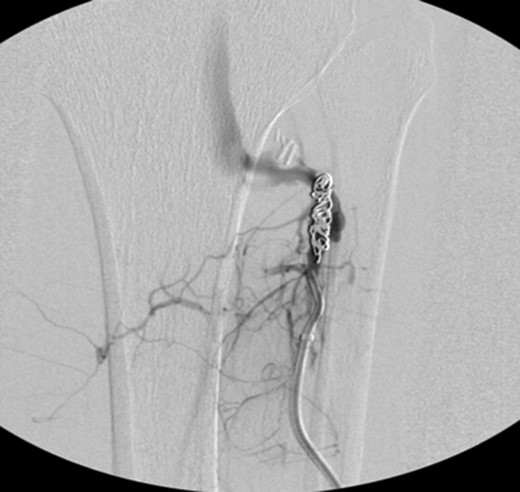

Patient underwent a left lower extremity angiogram. During the procedure she was found to have patent aorta and bilateral common iliac artery. There was no disease visualized in the left external iliac artery, common femoral artery (CFA), SFA, patent previously placed stent, patent above and below the knee PA and two vessel run off to the foot (Fig. 1). Upon delayed fluoroscopic images we identified contrast filling the deep venous system rather quickly suggesting a high volume fistula (Fig. 2). We then identified the fistula between ATA and ATV. Although ATA was previously ligated there was retrograde filling of the artery from unnamed branches, which communicated with the venous system as shown in. In the midcalf (ATA) was cannulated with a micropuncture needle. Micropuncture wire was inserted and a 5-Fr sheath was inserted after exchanging over wire. At this point VortX coils (Boston Scientific) were placed from the curve of ATA until the whole AVF was sealed. Anterograde angiogram showed no flow through the fistula (Figs 3 and 4). There was a palpable PT and DP pulse at the completion of the procedure. Sheath was removed, pressure dressing applied. Patient was discharged home same day. Recovery has been unremarkable. Three months follow-up claudication symptoms have significantly improved.

Anterograde angiogram showed no flow through the fistula tract with two vessels run off.